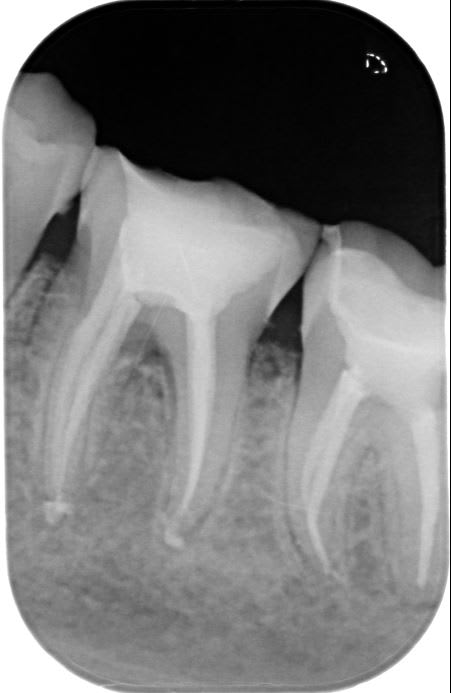

J'ai dévitalisé une 36 nécrosée à cause d'une fêlure en linguale... La patiente n'avait pas eu de signes d'appel avant les fortes douleurs dues à la nécrose.

Lors de la dévitalisation, j'ai été surprise à la radio par la largeur du trait de fêlure qui ne correspond pas à ce que je vois avec mes loupes ( zeiss x2.5)

Je n'ai pas non plus de fêlure au niveau du plancher pulpaire mais je vois bien une fêlure qui continue un peu sous la gencive linguale.

A priori elle est pas fêlée mais fendue si j'en crois la radio lime en place....

Donc pas possible de garder la dent en l'état.

Pas de précipitation d'autant que le trait de fracture rejoint la racine mésial (c'est peut être l'incidence de la rx qui fait croire ca) donc séparer les racines et mettre sous provisoire et attendre de 6 à 12 mois